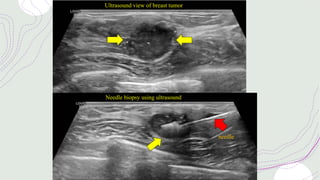

Ultrasound view of breast tumor

Needle biopsy using ultrasound

needle

Ultrasound view ofbreast tumor Needle biopsy using ultrasound needle